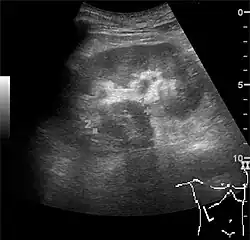

Figure 15. End-stage hydronephrosis with cortical thinning. Measurement of pelvic dilatation on the US image is illustrated by '+' and a dashed line.[1] -

Figure 16. Hydronephrosis with dilated anechoic pelvis and calyces, along with cortical atrophy. The width of a calyx is measured on the US image in the longitudinal scan plane, and illustrated by '+' and a dashed line.[1] -

Figure 17. Same patient as in Figure 16 with measurement of the pelvis dilation in the transverse scan plane illustrated on the US image with '+' and a dashed line.[1]